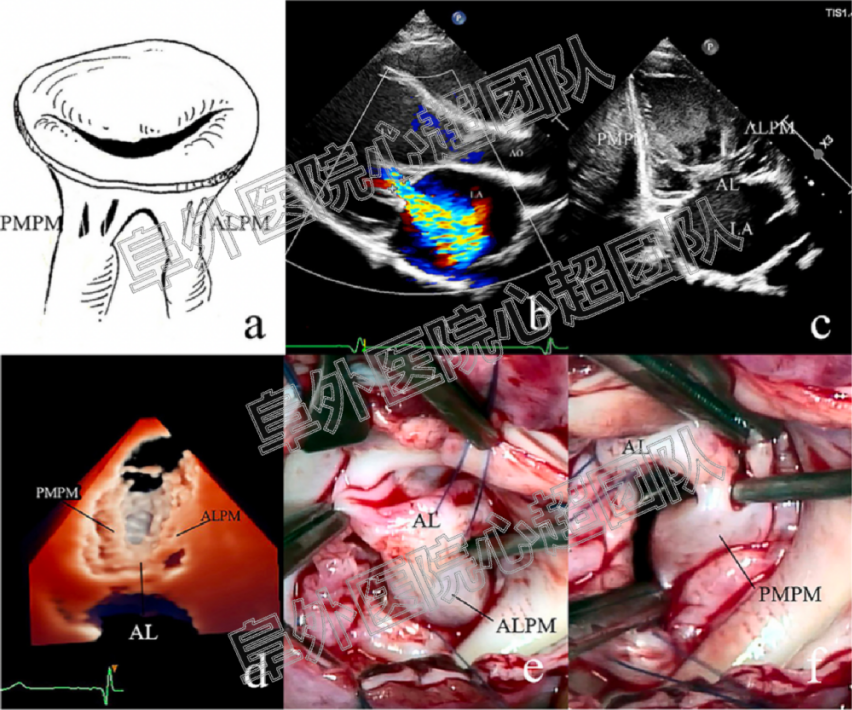

1. 共纳入207例患者,86例患儿超声诊断为UCMV(41.6%),其中77例接受了二尖瓣成形手术:75例通过手术明确诊断为UCMV(40.5%),1例患儿诊断为二尖瓣脱垂,1例患儿为功能性MR。121例患儿超声诊断其他类型的二尖瓣病变,其中110例进行了二尖瓣成形或置换手术。对于UCMV病变的诊断超声和手术结果呈现较高的一致性(kappa = 0.857, p < 0.001)。下图分别显示三种类型的UCMV的二维和三维超声心动图以及术中探查的结果。

Class III

UCMV疾病谱涵盖了二尖瓣拱廊及其一系列相关的非典型病变(如半二尖瓣拱廊、部分吊床样二尖瓣),其胚胎学机制被认为是二尖瓣在胶原化腱索衰减和延长之前发育停滞的结果。根据病变腱索的情况及是否合并MS,将UCMV分为三型,从I型到III型病变的程度是逐渐加重的,这表明二尖瓣腱索发育停止发生的时间越来越早,因此,III型患者的二尖瓣功能障碍更重,手术预后更差。典型二尖瓣拱廊的解剖与UCMV III型以及一部分II型是相似的。拱廊由两组肥厚的乳头肌和纤维桥组成,纤维桥由二尖瓣前叶增厚的下缘和中间的腱索组成。纤维桥在某些患者中并不典型,因此不作为UCMV的诊断标准。典型的先天性MS归属于III型UCMV。UCMV的另一个显著特点是所有的类型中ALCT都与腱索分布不良相关,而不存在PMCT单独病变的情况,可能是由于PMCT的腱索发育较ALCT完成的更早。UCMV I型的解剖特点和既往文献中所描述的降落伞样二尖瓣的病变是非常相似的。因此,我们认为,UCMV构成了儿童二尖瓣发育不良的主要发病机制。肥大延长的乳头肌和明显缩短或缺失的腱索,导致瓣叶的移位,瓣叶运动受限、对合缘较少从而引起二尖瓣返流或狭窄。